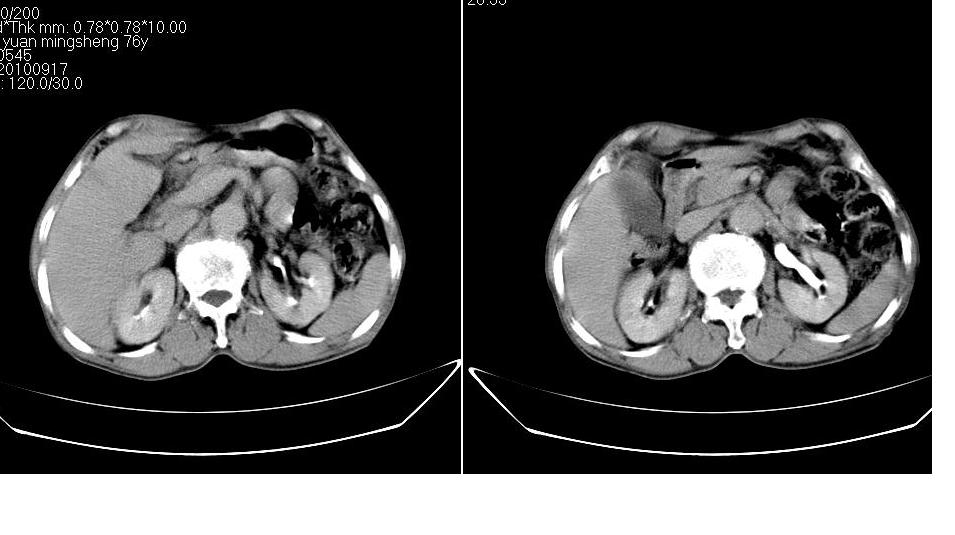

男,76岁,上腹部疼二天来就诊,彩超提示肝左叶占位,随后做上腹部ct平扫,今天做上腹部ct增强扫描,手工推药,效果不好,请谅解。

肝左叶s4肿块强化形式大概是:慢进慢出,逐渐强化----考虑血管瘤/腺瘤?{动脉期应更提前扫}。

肝右叶前段hcc

1)肝右叶前段低密度灶,不排除肝癌可能;建议查afp。2)右肾上极囊肿。

肝内胆管积气扩张,胆囊增大,肝右前叶低密度灶,逐渐强化,一元论,胆系感染,局限性肝脓肿;右肾囊肿。

考虑肝s4段肝脓肿可能?未排除肝癌。右肾上极囊肿。